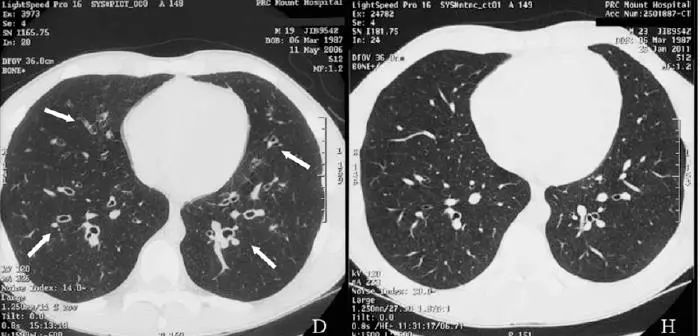

再来看看一个歪国人的病例——

we report a case of a previously healthy 19-year-old man,a professional basketball player with no antecedent history of smoking or lung disease。

19岁boy,专业级别的篮球运动员,既往不抽烟,没有肺病。

Initially, he had nonproductive repetitive cough for 1 month and was diagnosed with pertussis infection on positive serology.

起初干咳了一个月,诊断为百日咳。

Later, his cough became productive with purulent sputum.

后来咳脓痰。

At this stage, he also had exertional wheezing, significant weight loss,fever, sweats, and decline in exercise tolerance.

这阶段,患者出现运动后喘息,体重下降,发热,出汗,运动耐力下降。

Prior to presentation to our pulmonology clinic, he had received multiple courses of antibiotics,including macrolides, for presumed recurrent bronchopneumonia

with minimal response.

外院推测是反复患肺炎,所以反复抗感染治疗,包括大环内酯类抗生素,然而,并没有什么鸟用。

Immunoglobulin levels (including total IgE), allergen-specific IgE levels, Aspergillus precipitins, allergen skin tests, autoimmune markers, and T-cell phenotypes were all normal.

曲霉抗原皮试、血清总lgE等等各种检查正常,不支持变应性支气管肺曲霉病。

Diagnosis of postinfective bronchiectasis was made and the patient was treated with low-dose oral prednisolone for 4 weeks, budesonide–eformoterol, and sodium cromoglycate inhalers.

诊断:感染后支扩

治疗:泼尼松龙 4周,布地奈德福莫特罗、色甘酸钠吸入

He adhered to treatment and significant improvement in symptoms was noted over 6

months. At a review 2 years later, he had complete resolution of symptoms and further improvement in spirometry values , and repeat high-resolution computed tomography showed no evidence of previously noted dilated airways.

病人坚持治疗,6月后症状好转,2年后,各方面都好转,连支气管扩张都好了!

This case highlights the fact that not all radiological postinfective bronchiectatic changes should be considered as irreversible.Early effective therapy should be provided and the patient monitored for resolution。

事实胜于雄辩,影像学发现的支扩,并不都是不可逆的。早期治疗,随访,有希望缓解。

下面是作者提供的精彩图谱,什么时候,国内的文献也有图,有稍微清晰一点的图。